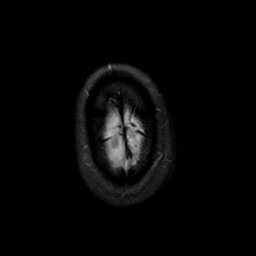

MR Study #19, August 25, 1991 -- Slice #47

[Home][Help][Clinical][Tour 1][Tour 2] Slice 47